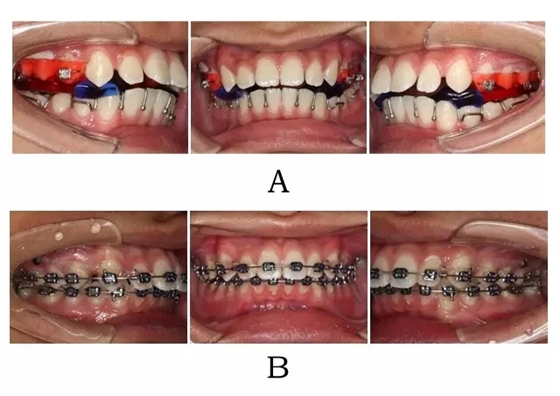

640.webp (5).jpg

圖 4-5:混合 I I 型突面畸形 SGTB 矯形及后期常規(guī)固定矯治。

(A)SGTB 矯形 (B)后期固定矯治

Figure 4-5. SGTB therapy for merged prognathism (Type II). (A) SGTB orthopedics at early stage.(B) Fixed orthodontics at late stage.